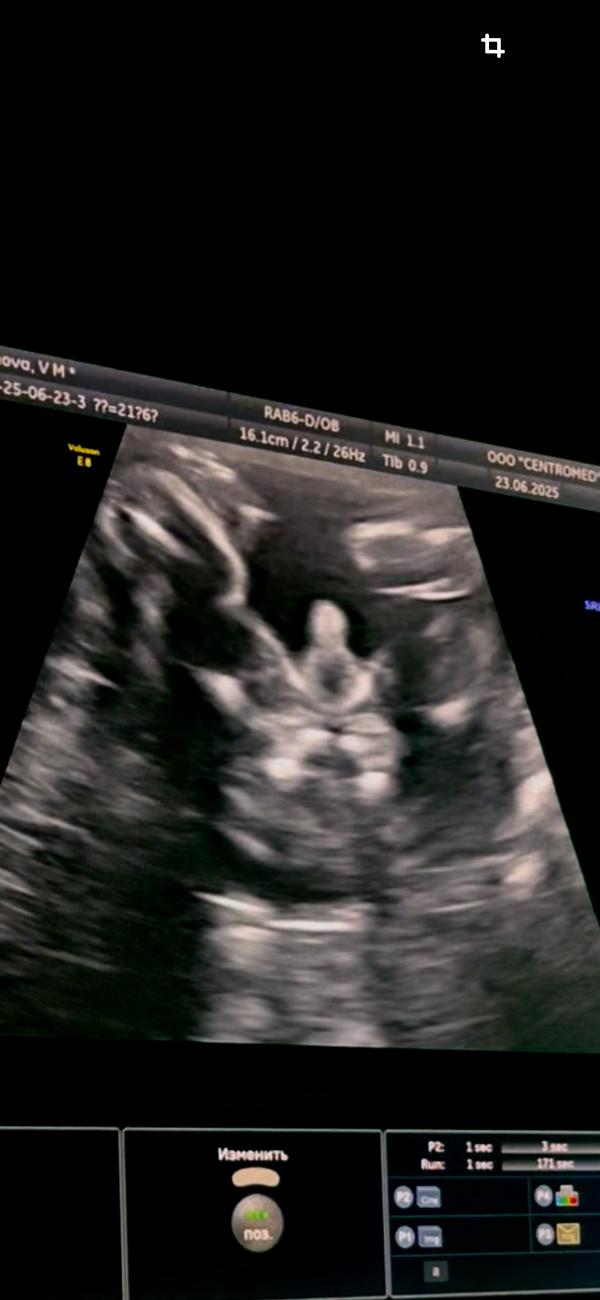

вспомнила как мы после нашего гендер-пати сходили с мужем платно на узи, так как муж тоже хотел посмотреть на малыша, ону перед узи муж в шутку малышу сказал чтобы показал свою пипирку 🤣 и знаете что? наш мальчик сходу показал свою пипирку 😂

как раз еще день рождения мужа было 🥰